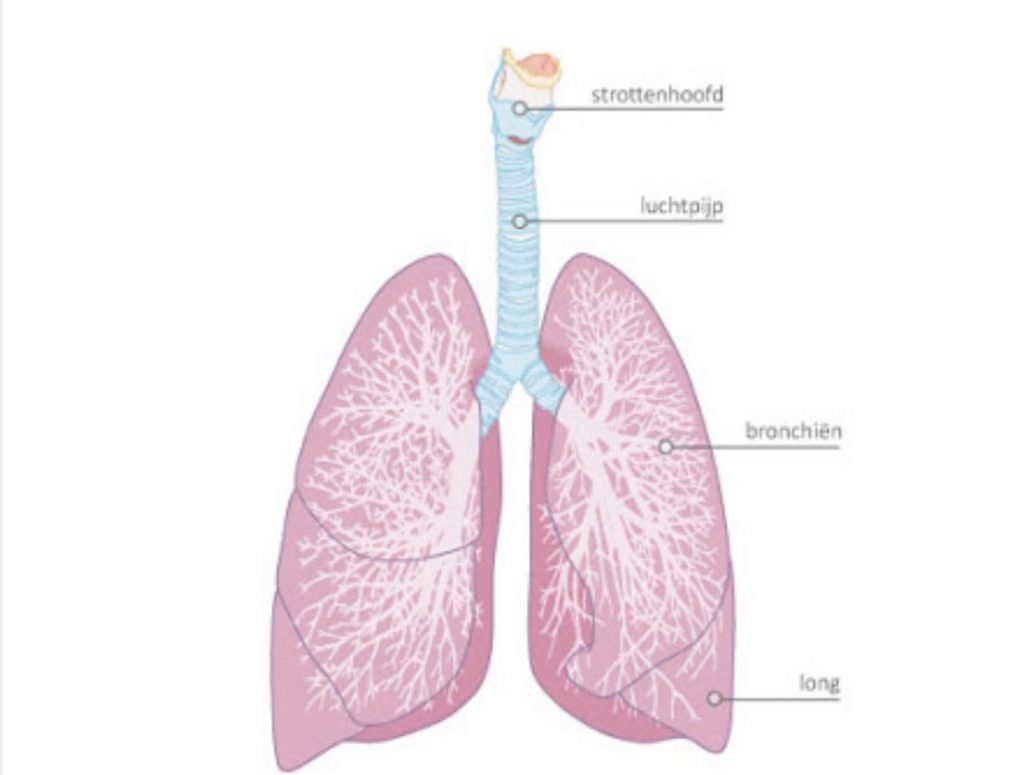

Ons ademhalingsstelsel bestaat grof gezegd uit twee delen: de luchtwegen (of bronchieën) en de longen zelf waarin de longblaasjes (alveoli) liggen.i pic.twitter.com/jBgOrBcAve

De luchtwegen (bronchieen) zorgen voor het transport van zuurstof naar de longblaasjes.